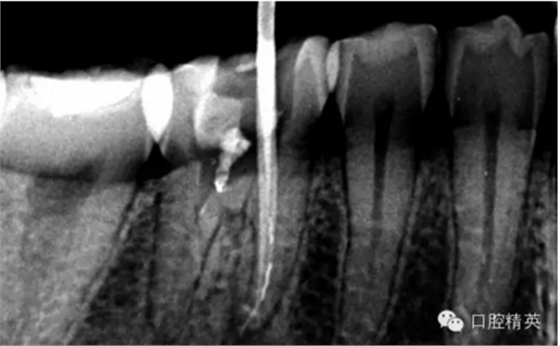

下面我來分享一下我近期的一個鈣化根管病例:

患者,肖某,男,32歲,#36慢性牙髓炎。遠(yuǎn)中舌根根尖1/3彎曲而且鈣化不通,我用盡辦法疏通了很久也沒到達WL,(我一直在幻想,要是有超聲系統(tǒng)該多好,可是現(xiàn)實很骨感,我們單位暫時還沒有超聲系統(tǒng)),后來我放棄了,最后的根充片顯示遠(yuǎn)中舌根充填物距根尖端2.84mm,屬于欠填范圍(根管內(nèi)充填物距根尖端2mm以上),其它三根根尖1/3鈣化相對沒那么嚴(yán)重,根充片顯示屬于恰填范圍(根管內(nèi)充填物距根尖端0.5~2mm)。歡迎網(wǎng)友們針對這個病例提出寶貴的建議!